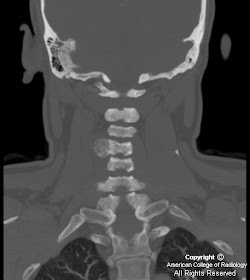

Figure 2 and Figure 3: Coronal and sagittal MIP CT images demonstrate that the expansile portion of the lesion involves the transverse process, facet and lamina with sparing of the vertebral body.